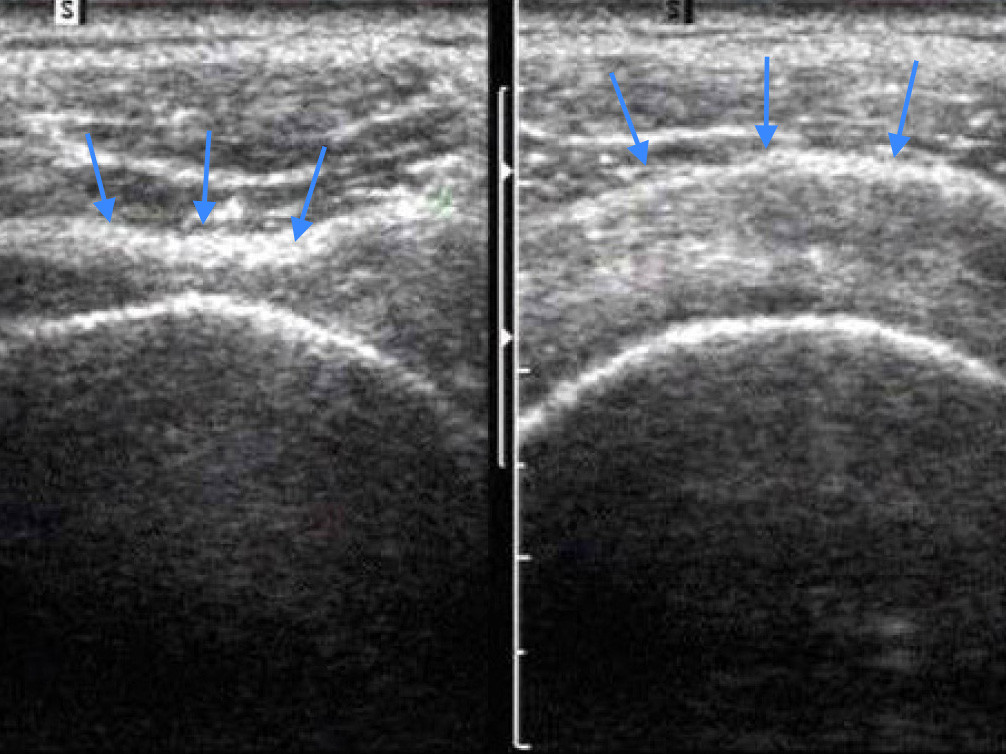

Dieses Bild zeigt Ultraschallbilder von beiden Schultern: Das linke Bild zeigt ein Rotatorenmanschettendefekt (Loch) mit einem Durchhängen der Rotatorenmanschette (Pfeile). Das rechte Bild eine runde gesunde Rotatorenmanschette